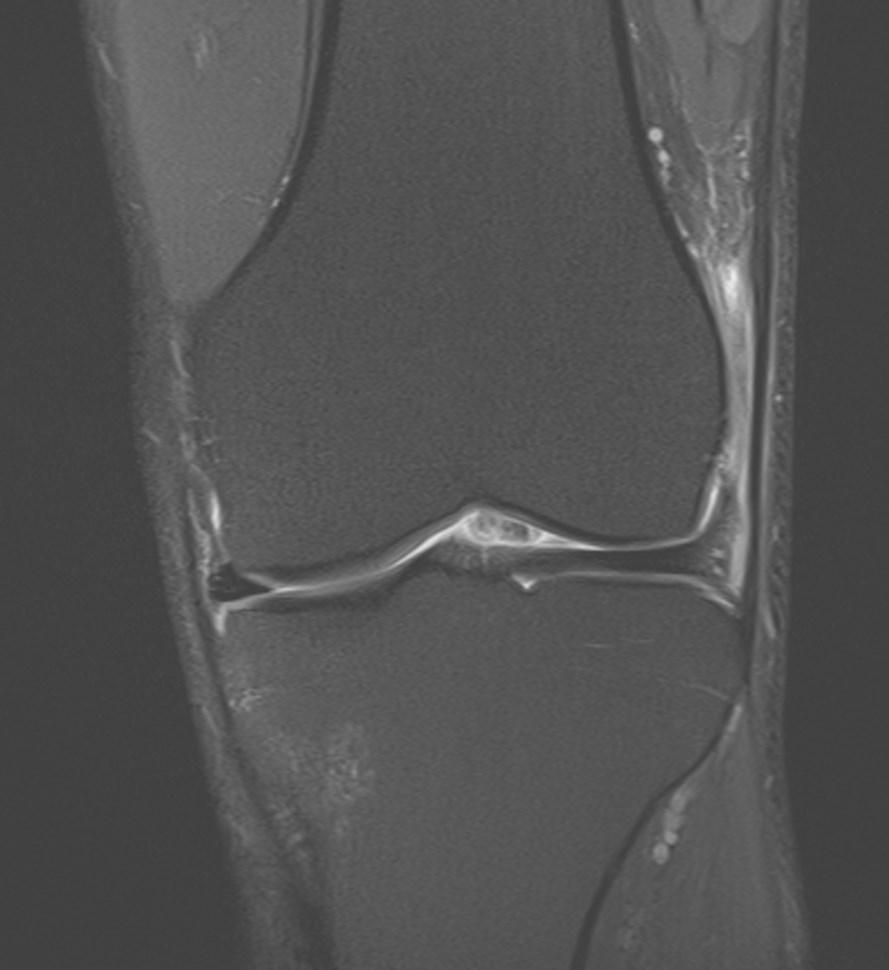

*49-year-old male present with pain above the lateral margin of the knee.

What is the most likely diagnosis?

Answer: Iliotibial band (friction) syndrome

MR images revealed high signal intensity in the fluid sensitive sequences involving the fat planes between the iliotibial band and lateral femoral condyle. There is no significant thickening of the iliotibial band or abnormal signal intensity.

Iliotibial band syndrome is a common cause of lateral knee pain related to intense physical activity resulting in chronic inflammation.

Differential diagnosis: lateral meniscal tear, lateral collateral ligament injury